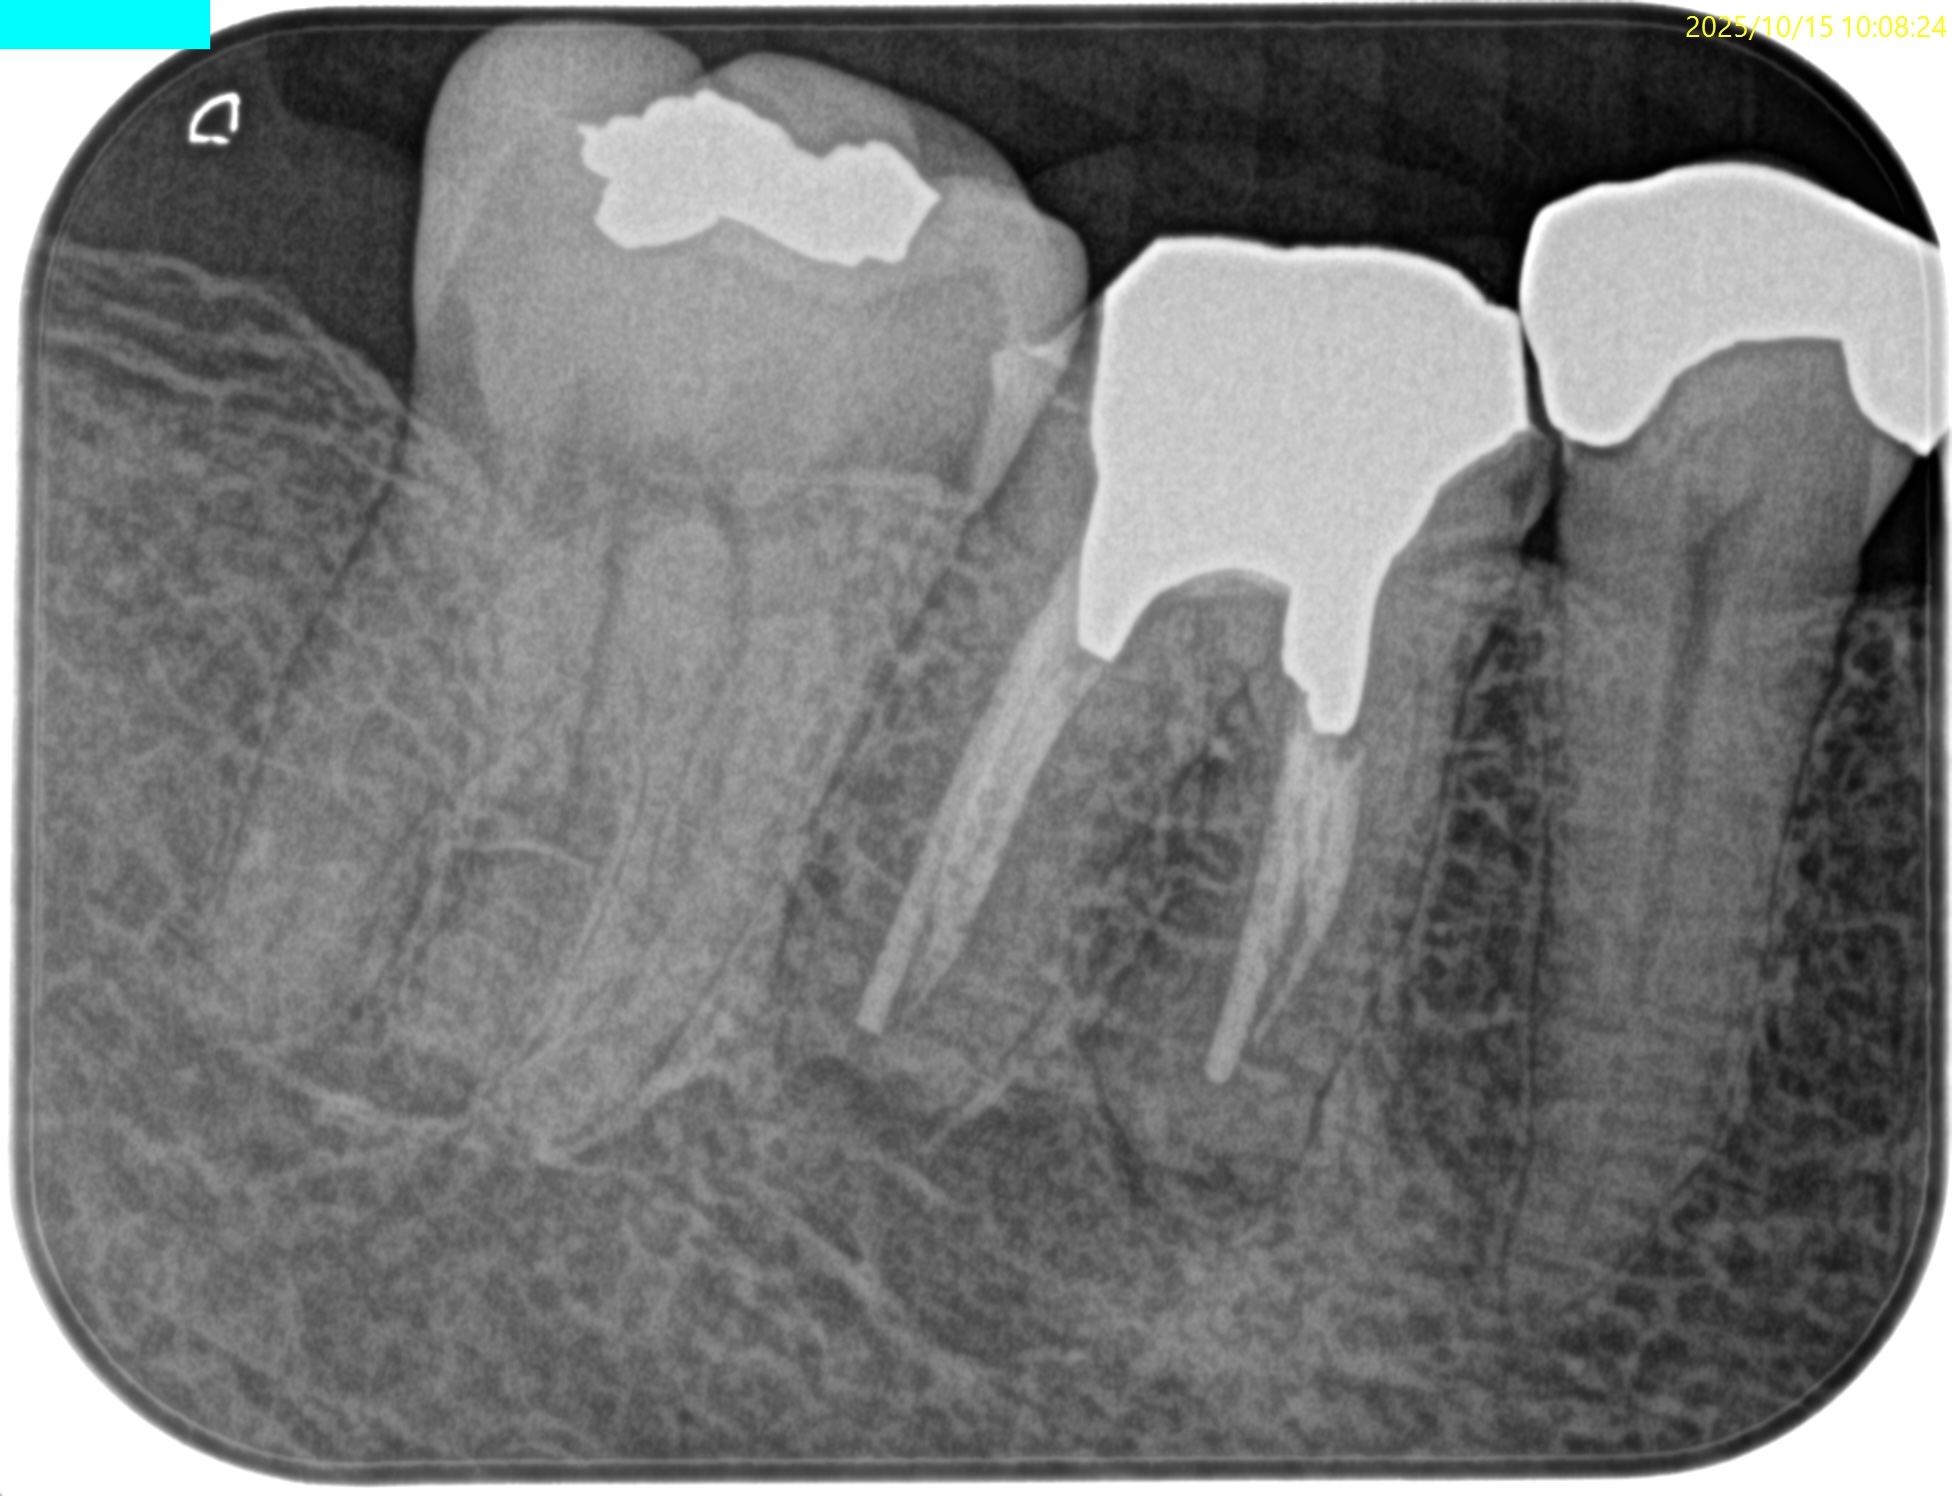

PA(2025.10.15)

CBCT(2025.10.15)

#30 MB

#30 ML

#30 D